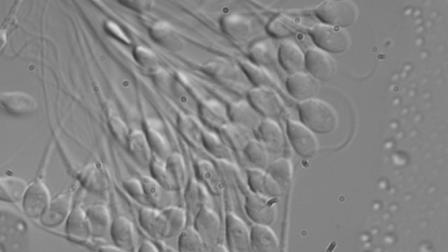

En 1967 el científico británico Robert Edwards consiguió el primer éxito en la fecundación in vitro de un óvulo humano. Sin embargo, el primer embarazo de un niño “ajeno” que desgraciadamente fue extrauterino se produjo en 1976, después de nueve largos años de investigaciones y experimentos sin cesar.

En 1967 el científico británico Robert Edwards consiguió el primer éxito en la fecundación in vitro de un óvulo humano.